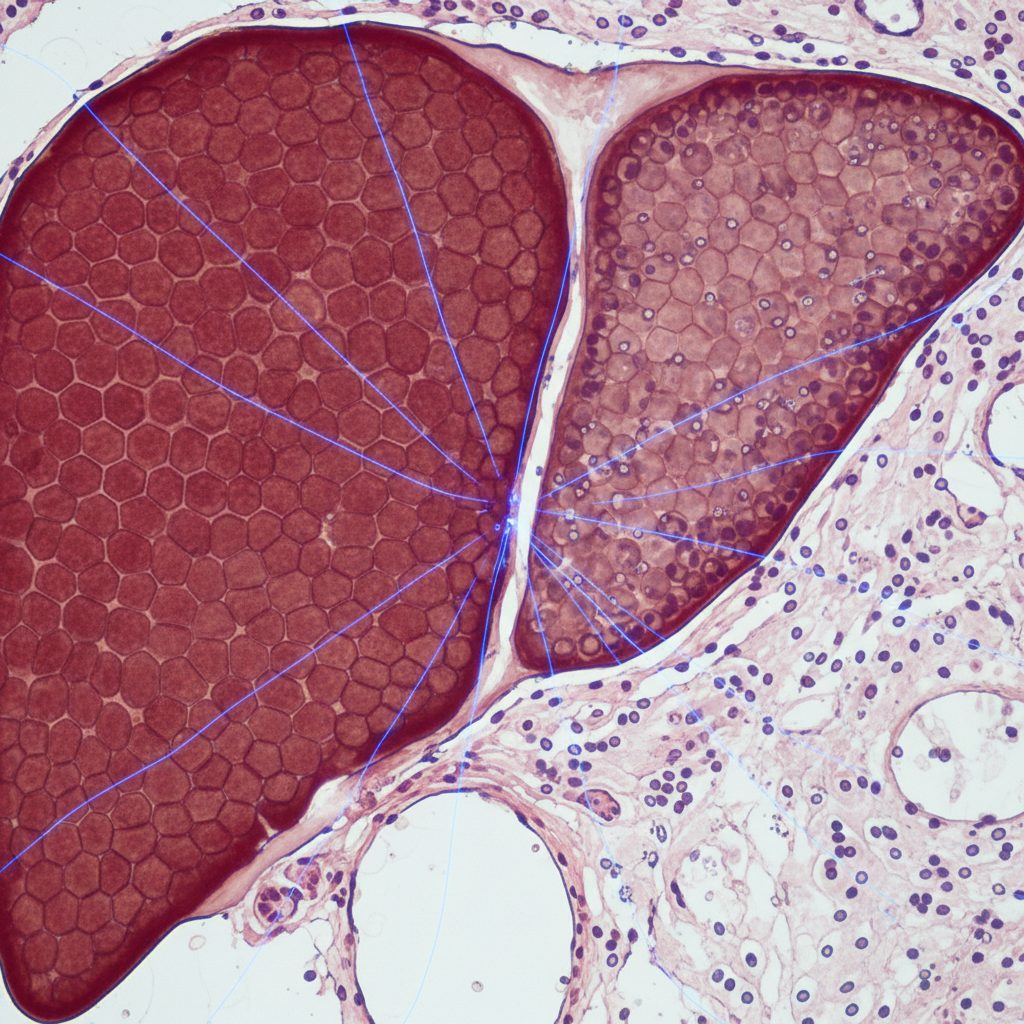

Metabolic health extends far beyond weight control. A key area of research focuses on liver health, especially a condition called Metabolic Dysfunction-Associated Steatohepatitis (MASH).

MASH occurs when fat accumulates in the liver, leading to inflammation and scarring. It is linked to obesity, insulin resistance, and poor metabolic health rather than alcohol use.

Studies show that GLP-1-based therapies, such as semaglutide, can reduce liver fat and improve liver function. In patients with moderate or advanced MASH, semaglutide has demonstrated measurable improvement in liver tissue and function.